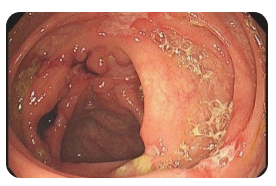

🍽️ 왼쪽 옆구리 통증 소화불량

소화불량은 위장 기능 저하로 인해 복부 불쾌감과 함께 옆구리 통증을 유발할 수 있습니다. 특히 식사 후 통증이 나타난다면 위염이나 위궤양, 장운동 이상을 의심할 수 있습니다. 복부 팽만, 잦은 트림, 속쓰림 등의 증상이 함께 나타날 수 있으며, 불규칙한 식습관과 스트레스가 원인이 될 수 있습니다. 증상이 지속된다면 내시경 검사를 통해 위장 질환을 확인하는 것이 필요합니다.